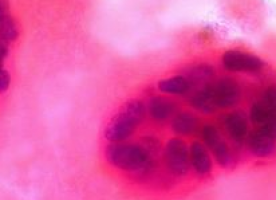

Utilizando varios ensayos nuevos para modelar la metástasis en el laboratorio, así como experimentos en ratones, los investigadores descubrieron que, después de encontrar células tumorales, las células NK humanas y de ratones pierden la capacidad de restringir la invasión tumoral y en su lugar ayudan a las células cancerosas a formar nuevos tumores.

Las células NK expuestas a los tumores experimentan cambios dramáticos, activando y desactivando miles de genes y expresando diferentes proteínas receptoras en su superficie.